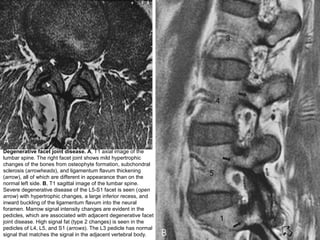

Degenerative facet joint disease. A, T1 axial image of the

lumbar spine. The right facet joint shows mild hypertrophic

changes of the bones from osteophyte formation, subchondral

sclerosis (arrowheads), and ligamentum flavum thickening

(arrow), all of which are different in appearance than on the

normal left side. B, T1 sagittal image of the lumbar spine.

Severe degenerative disease of the L5-S1 facet is seen (open

arrow) with hypertrophic changes, a large inferior recess, and

inward buckling of the ligamentum flavum into the neural

foramen. Marrow signal intensity changes are evident in the

pedicles, which are associated with adjacent degenerative facet

joint disease. High signal fat (type 2 changes) is seen in the

pedicles of L4, L5, and S1 (arrows). The L3 pedicle has normal

signal that matches the signal in the adjacent vertebral body.